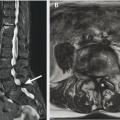

Réduction du calibre du canal rachidien lombaire sur un ou plusieurs étages, liée le plus souvent à des remaniements dégénératifs (fig. 1) :

Diagnostic confirmé par IRM ou scanner du rachis lombaire :

– contrairement au canal étroit constitutionnel, la sténose est plutôt segmentaire (touchant 1 ou 2 étages seulement, fig. 2 et le plus souvent centrale (segment disco-articulaire) et latérale (défilé disco-articulaire, récessus latéral ou foraminal) ;